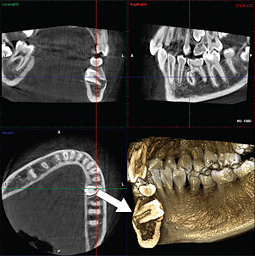

親知らずの抜歯

親知らずを安全に抜歯するためには、あごの中を通る神経や隣の歯との位置関係を正確に把握することが重要です。CT撮影を行うことで、それらをより明確に確認できます。

あごの骨・関節の診断

あごの骨や関節は、通常のレントゲン撮影では詳細が分かりにくい場合があります。CT撮影を行うことで、関節の変形などをより具体的に調べることができます。

埋伏歯の診断

あごの中に埋まっている歯の位置や向きを立体的に診断できます。